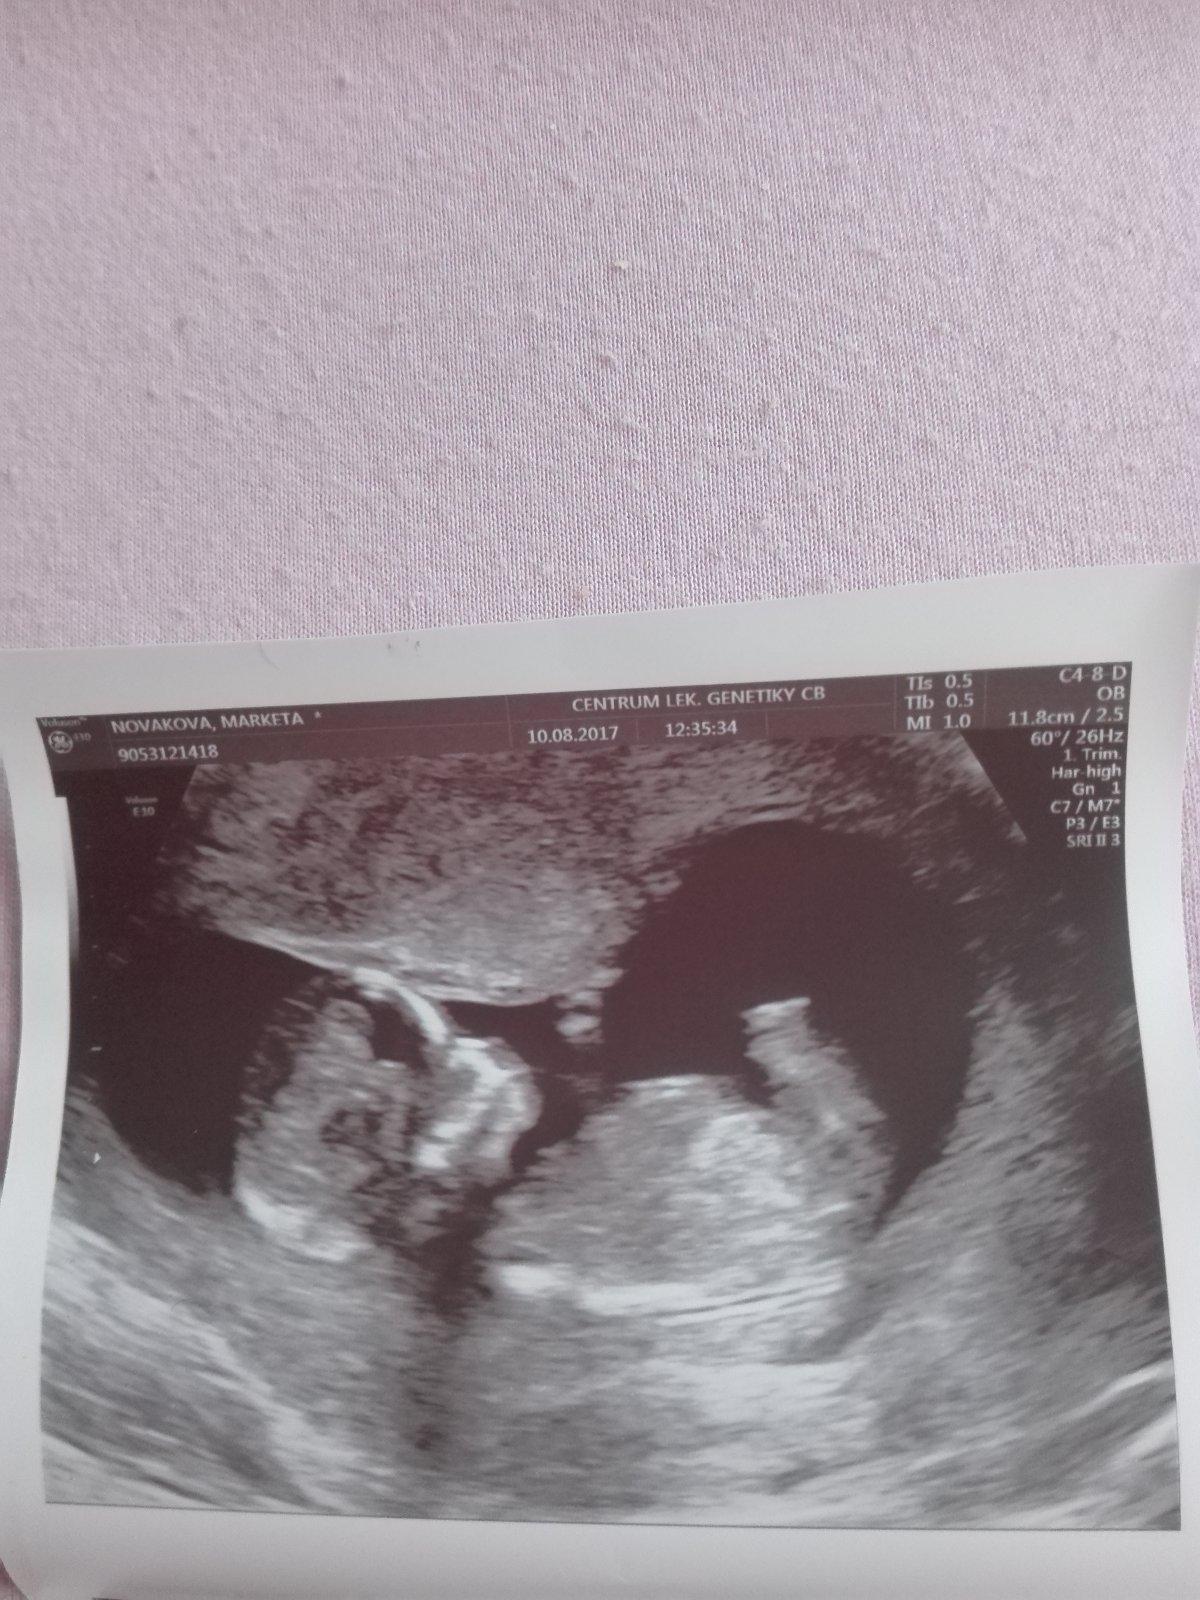

Jinak holky já jsem dnes po screeningu,ačkoli mimčo je menší(11+5)ale krásně roste a má se čile k světu. Ani nevíte jak jsem se v čekárně bála,jak u maturity. Naštěstí to ze mě spadlo

@mari90 nadherna fotka.